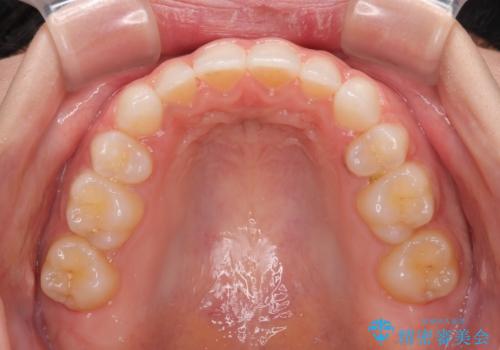

- 前歯のデコボコとクロスバイトを気にして来院された患者様です。

上下ともにデコボコはそれほど強くありませんでしたが、非抜歯では口元が突出した仕上がりとなる可能性があるため、上下左右の第一小臼歯4本を抜歯し、ワイヤー装置での抜歯矯正を行うこととしました

スペースを閉じるために期間を要しましたが、無事に綺麗な口元に仕上げることができました。